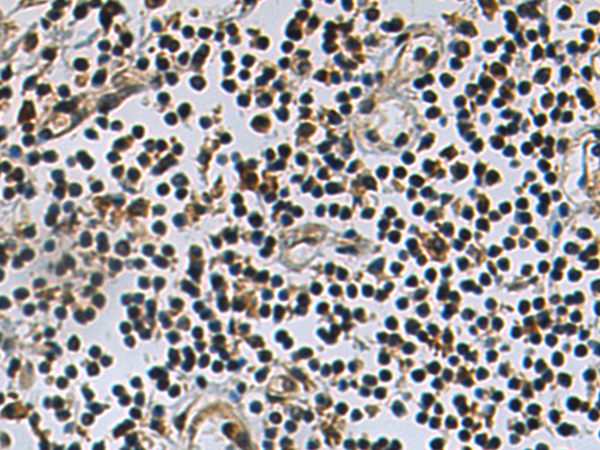

IHC positive control: |

Human breast cancer and Human prostate cancer |

IHC Recommend dilution: |

50-200 |